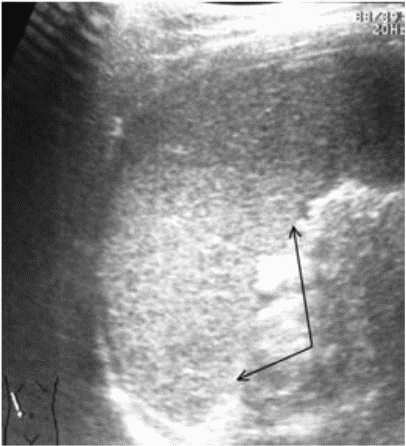

Ушибы селезенки сопровождаются интерстициальным отеком и геморрагическим пропитыванием тканей. Прямыми эхографическими признаками в первые 3 - 5 часов после травмы являются снижение эхогенности паренхимы и четкости контура органа, а также "разреженность" эхоструктуры паренхимы. Геморрагическое пропитывание паренхимы манифестировало наличием гиперэхогенных зон с нечеткими размытыми контурами в области повреждения (рис. 1). Характерно увеличение размеров всей селезенки или преимущественно поврежденного сегмента с нарушением ее конфигурации. Результаты цветового допплеровского картирования свидетельствуют о снижении кровотока, степень которого коррелирует с выраженностью эхографических проявлений отека паренхимы.

Рис. 1. Ушиб селезенки. Зона геморрагического пропитывания указана стрелками.